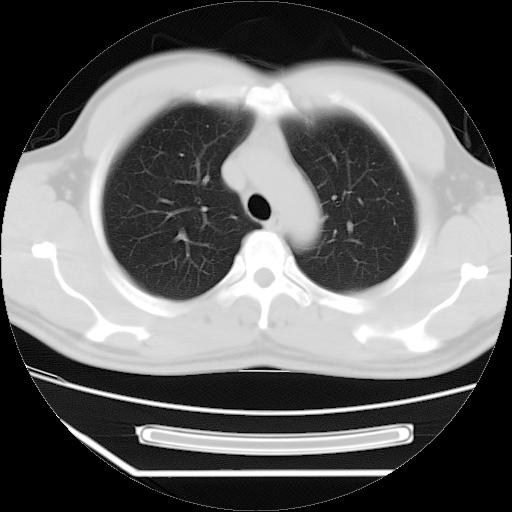

标题: CT21560:胸部肿块影,请会诊

男,38岁,于2009年8月9日晚突发左侧胸痛,今x线提示左下肺阴影,为了明显确诊断,行ct检查,

血常规:嗜酸性细胞增高,单核细胞增高。

病灶发生在下叶,密度均匀,边缘模糊、毛糙,周围血管纹理增强扭曲改变,靠近胸膜处病灶胸膜反应明显。

支持考虑---球形肺炎。

左肺舌叶病变。主体病灶呈类圆形中心密度低,成液化趋势周边班片影分布

考虑肺脓肿